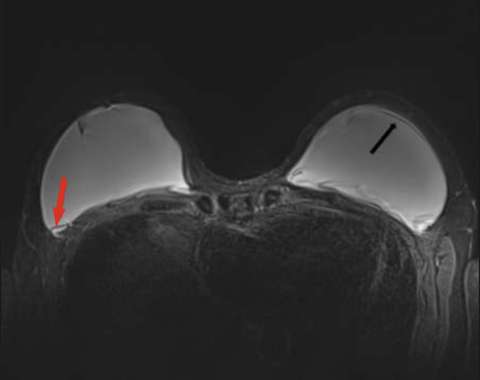

Minimally collapsed intracapsular rupture appears as a hypointense line that runs parallel to the fibrous capsule against the hyperintense extravasated silicone gelon silicone-sensitive MRI images, termed the “subcapsular line sign” (Figure 3).

Axial STIR MRI with arrows demonstrating subcapsular lines of bilateral intracapsular ruptures.

Figure 3: Axial STIR MRI with arrows demonstrating subcapsular lines of bilateral intracapsular ruptures.

Figure 6: Axial T2-weighted image showing a teardrop sign of intracapsular rupture (red arrow) and subscapular line sign (black arrow).